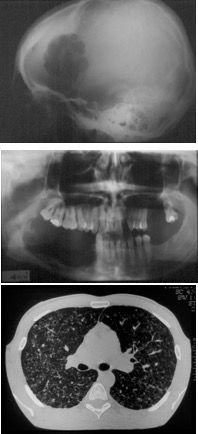

le bilan radiologique retrouve un aspect évocateur avec une lacune irrégulière, d’aspect mité, avec souvent une prise de contraste méningée en regard. on réalise un bilan systémique, en pratique le plus souvent limité à une scintigraphie du squelette.

du fait de cette présentation clinique et radiologique, il existe souvent une ambiguïté

avec une tumeur agressive de type sarcome qui justifie une prise en charge semi-urgente.